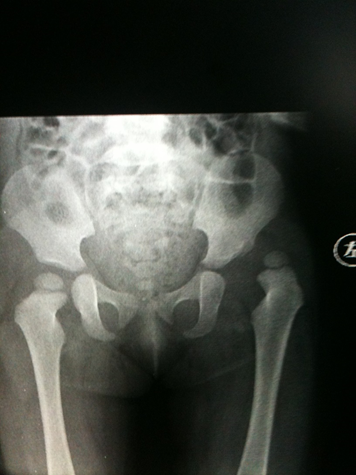

发育性髋关节脱位(DDH)是可能导致儿童残疾的重要疾病之一,也是对儿童骨科专家的重大挑战!幸运的是,目前在治疗此病,我还保持开放复位手术,从未发生再脱位。我无法确保以后手术,也一定不会发生再脱位,但是我一定会全力以赴、竭尽全力!手术效果展示:病例:黄佳X,女,2岁左DDH,行左侧髋关节开放复位(Pemberton)手术。术前X线片术后2月X线片术后1年X线片术后5年X线片